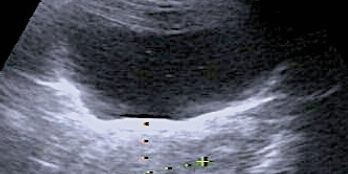

Image n°2 :

Cette vue ressemble à celle d’une échographie endovaginale.

Elle permet de mettre en évidence :

1/ un utérus de taille et de morphologie normales

2/ un endomètre fi n et régulier avec un très discrète lame liquidienne dessinant la cavité utérine

3/ enfin un ovaire d’aspect fonctionnel avec plusieurs follicules.

Tous ces éléments ont permis de rassurer la jeune fille et surtout sa mère.